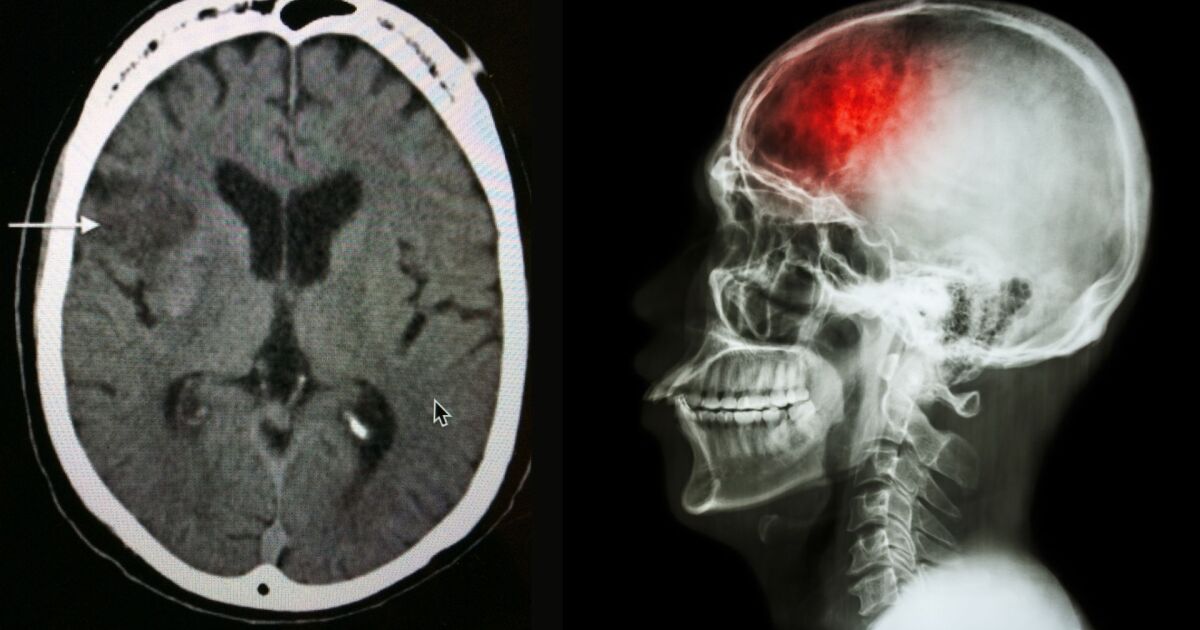

Преходните исхемични атаки (ПИА) възникват при временно блокиране на кръвоснабдяването на мозъка. За разлика от традиционния инсулт, симптомите при мини-инсулта обикновено преминават относително бързо, но това не означава, че няма дългосрочни последствия.

Първоначалната оценка е направена средно около 20 дни след появата на симптомите, като участниците са проследявани на 3, 6 и 12 месеца. За по-детайлна диагностика, всички пациенти са преминали през МРТ сканиране за установяване на наличие на остър инфаркт на мозъчна тъкан.